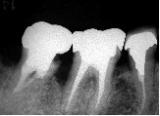

歯槽膿漏・X線写真 | ||

| 歯槽膿漏によって失われた骨(→印の部分)が再生しています。 | ![]() |

![]() |

【術前】 |

【術後】 |